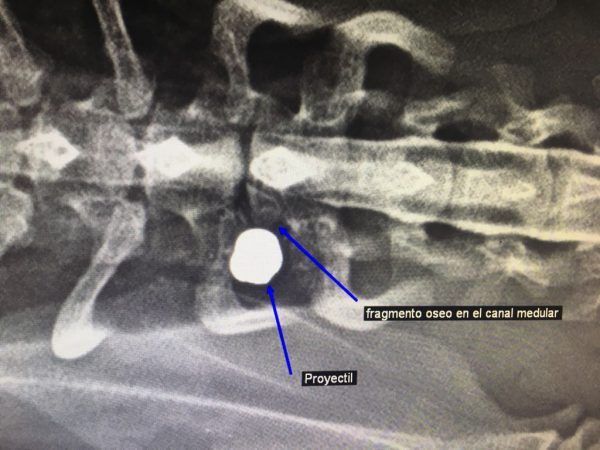

En la intervención quirúrgica, encontramos un perdigón impactado en la parte dorsal de la primera vértebra torácica, que había producido una fractura, con una esquirla que se había desplazado dentro del canal medular, comprimiendo severamente la médula espinal. Extrajimos el perdigón (foto 4) y el fragmento óseo, liberando de esta manera médula.